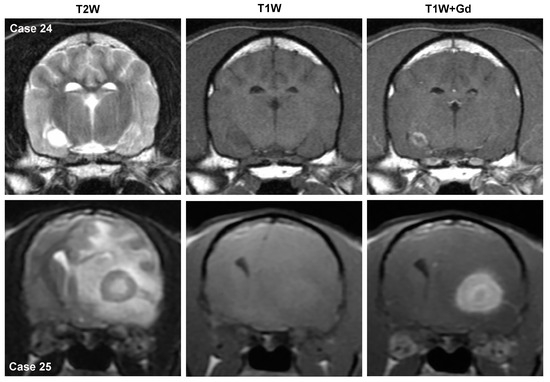

3.3.1. Gliomas (Astrocytoma, Oligodendroglioma, Undefined Glioma)

- Carloni, A.; Bernardini, M.; Mattei, C.; De Magistris, A.V.; Llabres-Diaz, F.; Williams, J.; Gutierrez-Quintana, R.; Oevermann, A.; Schweizer-Gorgas, D.; Finck, C.; et al. Can MRI differentiate between ring-enhancing gliomas and intra-axial abscesses? Vet. Radiol. Ultrasound 2022, 63, 563–572. [Google Scholar] [CrossRef] [PubMed]